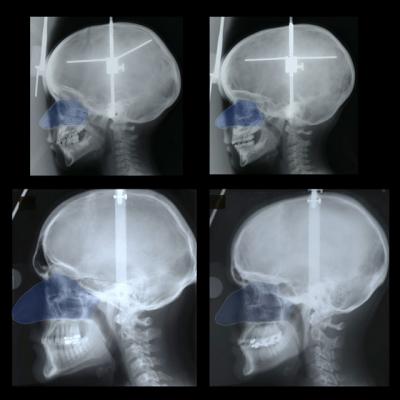

Holton and his team tracked nose size and growth of 38 individuals of European descent enrolled in the Iowa Facial Growth Study from three years of age until the mid-twenties, taking external and internal measurements at regular intervals for each individual. The researchers found that boys and girls have the same nose size, generally speaking, from birth until puberty percolated, around age 11. From that point onward, the size difference grew more pronounced, the measurements showed.